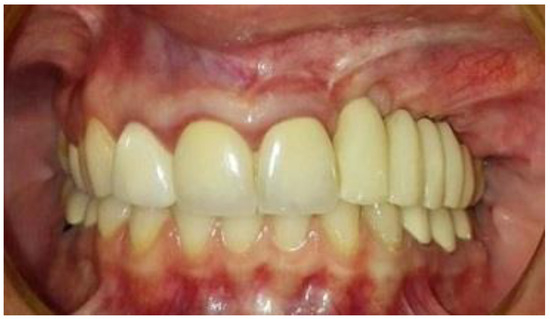

Figure 8. Temporary-fixed-prosthesis-supported dental implants. A good esthetical outcome is obvious.

The second-stage surgical intervention was carried out 6 months later for dental implant placement. Four implants (SPI-Alpha Bio Tec., Modi'in-Maccabim-Re'ut, Israel), 3.75 diameter/13 mm length, were placed in the new bone site in the left posterior maxilla (Figure 6b). The dental implants were uncovered 4 months thereafter (Figure 7). An acrylic bridge was fitted over the implants as a temporary prosthesis (Figure 8), and this was replaced 12 months later by a fixed ceramic prosthesis (Figure 9a,b). The patient was then followed over 7 years.

First surgery: Healing at the 4 weeks follow-up visit after the surgery was uneventful (Figure 5a,b). During dental implant placement surgery that was carried out six months after the first surgery, a good bone quality was observed with normal bleeding (Figure 6a). All implants were clinically and radiographically successfully osseointegrated when exposed 4 months later (Figure 7). The final rehabilitation after one year, and throughout the long period of the follow-up, provides satisfactory esthetic and functional outcomes (Figure 10a,b). There were no obvious changes in the lesion dimensions after 7 years (Figure 10c).